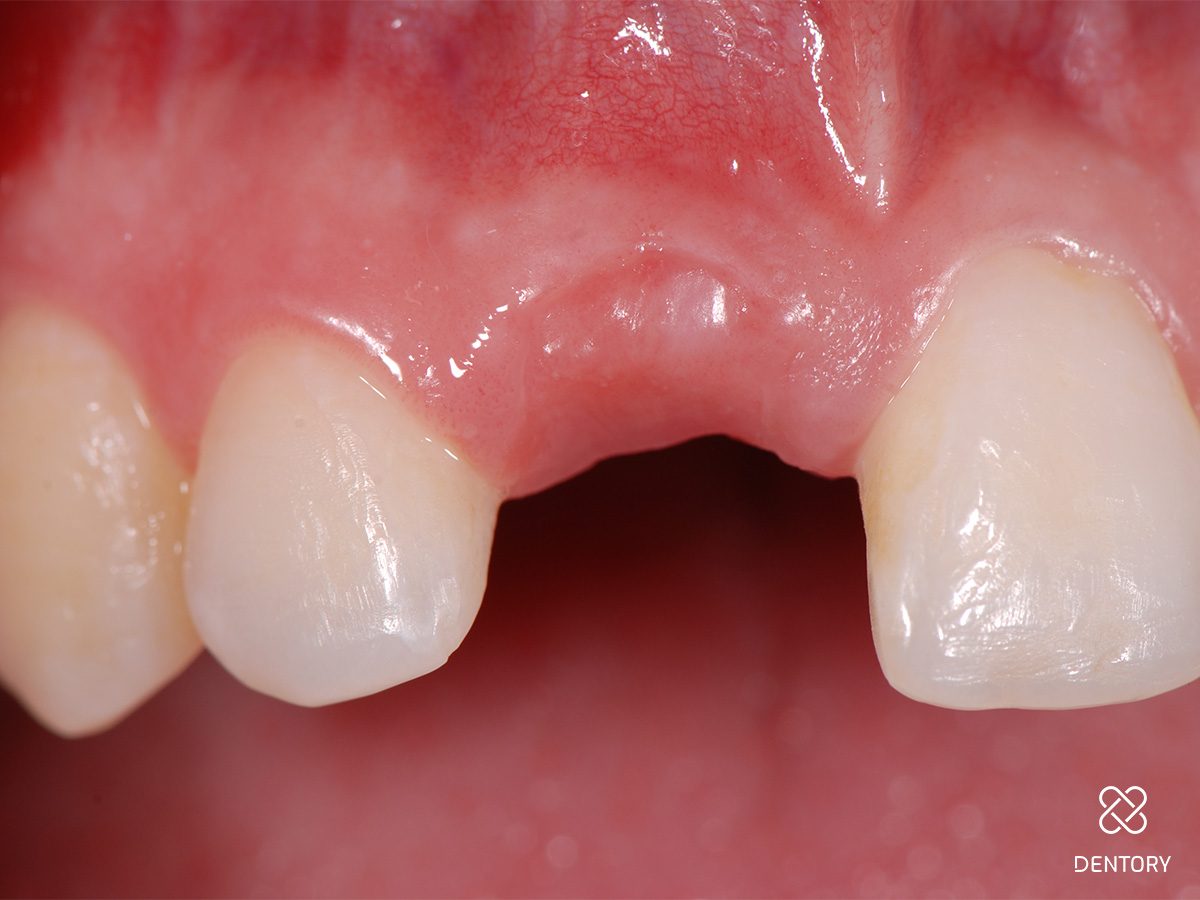

Abbildung 1

Ausgangssituation: Nicht erhaltungswürdiger Zahn 11 aufgrund einer externen Resorption.